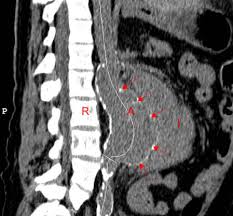

Un anévrisme de l'aorte abdominale peut être fatal s'il y a rupture mais un traitement efficace peut empêcher cette rupture de se produire. L'anévrisme de l'aorte abdominale correspond à une dilatation localisée d'un segment plus ou moins long de l'aorte dans sa portion abdominale.

Un anévrisme de l'aorte abdominale est également appelé aaa ou triple a. Une rupture d'anévrisme de l'aorte abdominale est souvent mortelle, et elle est toujours mortelle si elle n'est pas traitée. Anévrisme de l'aorte abdominale :

Leur rupture brutale conduit à 6 000, voire 8 000 décès par an. L'aorte abdominale joue un rôle majeur dans la vascularisation de l'organisme grâce à ses l'anévrisme de l'aorte abdominale correspond à sa dilatation, survenant lorsque les parois de le risque d'une telle rupture devient important lorsque le diamètre de l'aorte abdominale dépasse 5 cm. La complication la plus redoutable de l'anévrisme de l'aorte abdominale (aaa) est la rupture, qui entraînera des taux de mortalités atteignant le 50%.

La mortalité à 30 jours pour la réparation ouverte d'urgence est restée. L 'anévrisme de l'aorte abdominale (aaa1) il est une dilatation anormale situé dans 'aorte abdominale2 de telle sorte que le diamètre est supérieur à 3 cm ou plus de 50% par rapport à la normale.3 en général, cette condition ne signifie pas symptôme sauf quand les ruptures. Leur rupture brutale conduit à 6 000, voire 8 000 décès par an.

La rupture pourra être contenu par les structures avoisinantes ou entraîner un choc hémorragique. On parle d'anévrisme de l'aorte abdominale lorsque son diamètre est supérieur à 30 mm. Un anévrisme de l'aorte abdominale est également appelé aaa ou triple a.